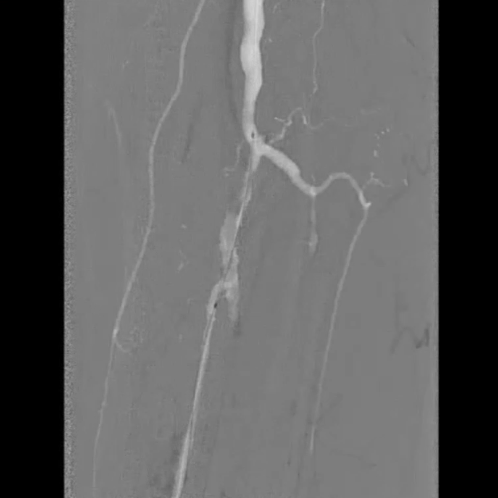

铁基可降解支架植入

按计划植入3×38mm载药铁基可降解支架,准确定位以完全覆盖病变;采用8 atm压力球囊扩张释放支架,确保支架充分张开。